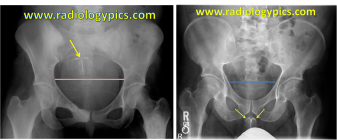

The following day, Keri Herman, fresh off the plane from an NBC Olympics shoot in LA, joins them. The trio migrates to a bigger jump. It’s 75 feet to the knuckle and after a few smooth tries, Christiansen goes too big, over-rotates and lands on her hip and hand. Herman and Raymond continue to session, moving from feature to feature until sunset. I miss all that as I drive Christiansen to the Vail Valley Medical Center where X-rays confirm that her hand is broken in three places. She’ll need surgery back home in Norway. The shoot’s over for Christiansen and so is her career long injury-free run.

The following day, Keri Herman, fresh off the plane from an NBC Olympics shoot in LA, joins them. The trio migrates to a bigger jump. It’s 75 feet to the knuckle and after a few smooth tries, Christiansen goes too big, over-rotates and lands on her hip and hand. Herman and Raymond continue to session, moving from feature to feature until sunset. I miss all that as I drive Christiansen to the Vail Valley Medical Center where X-rays confirm that her hand is broken in three places. She’ll need surgery back home in Norway. The shoot’s over for Christiansen and so is her career long injury-free run.